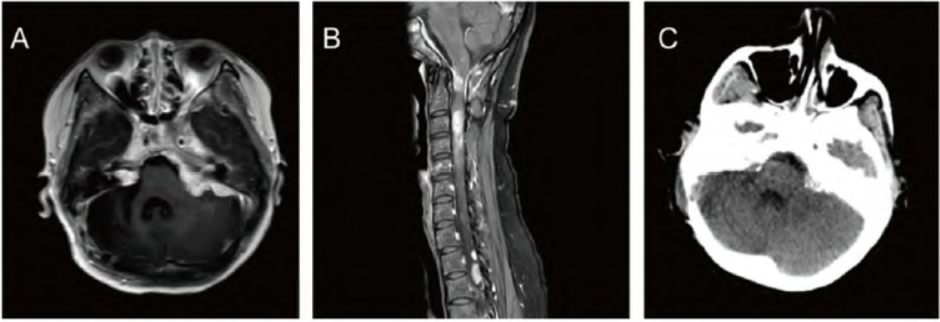

术后转入神经外科重症监护室继续治疗,头颅CT未见术区明显出血,肿瘤切除满意(图1C)。肿瘤组织病理证实左侧延髓占位为神经鞘瘤,右侧延髓占位为脑膜瘤(图1D)。免疫组化示:CD34(血管+),结蛋白(desmin)(-),平滑肌肌动蛋白(SMA)(灶+),EMA(部分+),Ki-67(4%+),PR(部分+),GFAP(-),S-100(部分+)(图1E),CD56(部分+),WT1(-),促生长素抑制蛋白受体2(SSTR2)(部分+),信号转导和转录激活因子6(STAT6)(-)。

图1 患者术前及术后影像学、病理结果。A. 术前头颅 MRI 增强图像,可见双侧桥小脑角及双侧中后颅窝颅底明显强化,强化多均匀;B. 术前颈椎 MRI 增强图像,可见椎管及双侧椎间孔内多发大小不等异常信号,星明显强化,较大者大小约30 mm× 10mm;C. 术后头颅CT平扫

,术区无明显出血,肿瘤切除满意;D. 右侧延髓肿瘤组织病理结果(HE染色 x100);E. 延髓肿瘤组织S-100 免疫组化结果(x100)。